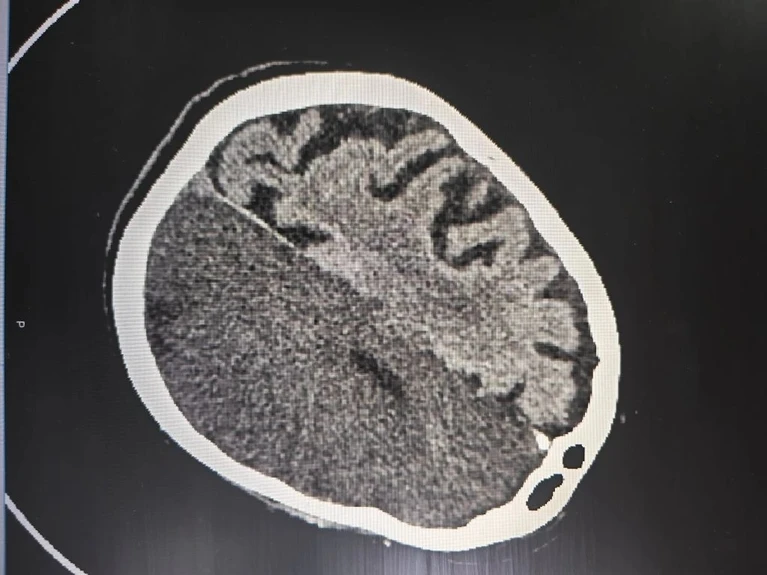

В стационаре женщине провели обследование. Компьютерная томография показала обширный ишемический инсульт, при котором произошло острое нарушение кровообращения и гибель клеток головного мозга. Этот случай является наиболее опасным, поскольку сопровождается высокой вероятностью неблагоприятных исходов.